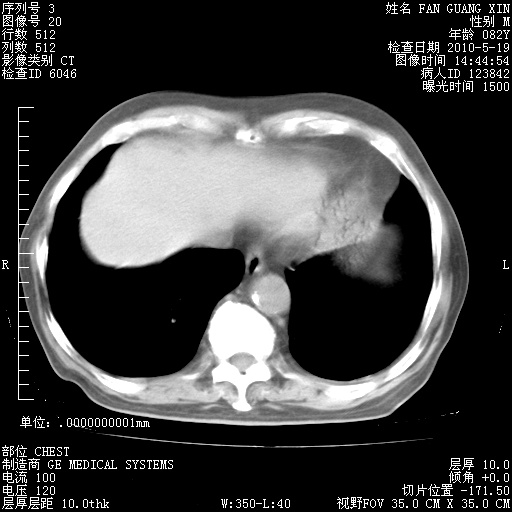

发表于 2010-5-19 19:23

还需要哪些辅助检查?我们医院排除真菌感染没有任何检验方法,胸片好像能够排除肺部真菌感染。

补充:ENA化验全部阴性。免疫五项(IgG、IgA、IgM、C3、C4)只有C4略高。